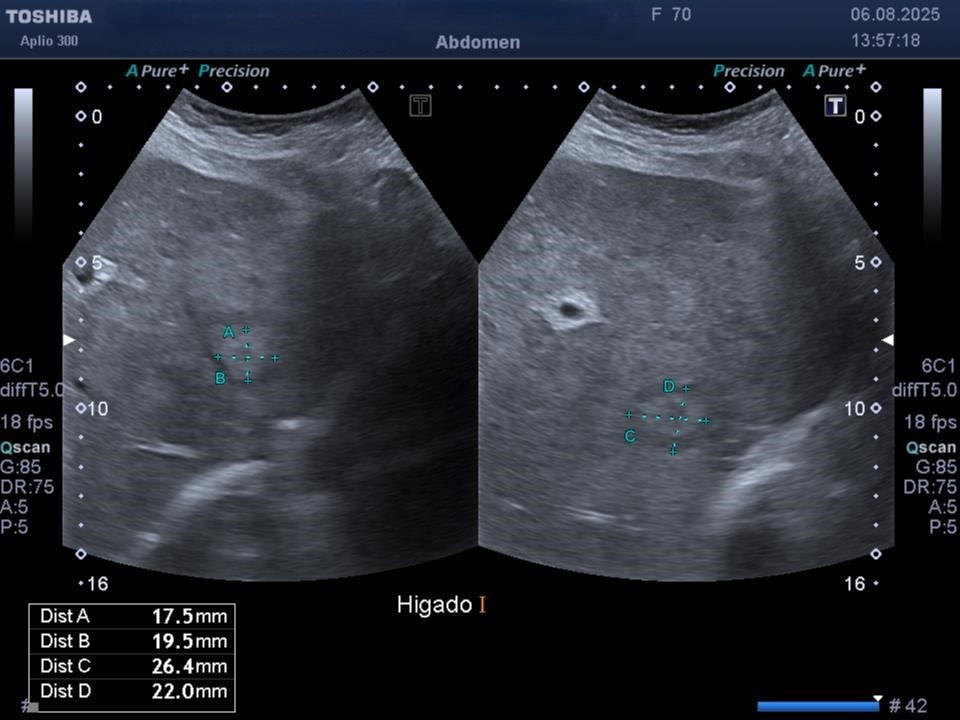

Se realiza una ecografía abdominal en la que se puede ver el hígado aumentado de tamaño, con parénquima heterogéneo y varias imágenes en forma de donut altamente sugestivas de metástasis hepáticas.